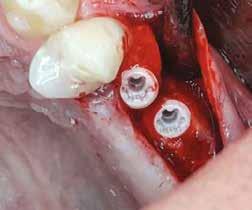

Mind a hat implantátum esetén kétlépcsős műtétet végeztünk. Minden sebészeti eljárást bódítás, illetve preoperatív szisztémás antibiotikus terápia nélkül végeztünk. A négy eset közül kettőnél leukocitában és vérlemezkében gazdag fibrint (L-PRF) alkalmaztunk a beavatkozás során (IntraSpin, BioHorizons; 2. táblázat). Minden esetben a pontos CERALOG menetvágási (maximum 15 ford./perc) és fúrási (maximális fúrási fordulatszám: 550–800 ford./perc) protokollt követtük. Az összes implantátumot manuálisan helyeztük be 35 Ncm maximális nyomatékkal. Az implantátumokba PEEK zárócsavar került (2. ábra). A lágyszövetet atraumatikus, felszívódó varrattal, szorosan zártuk/összevarrtuk. A műtétek után szövődmények nem jelentkeztek. A pácienseket arra kértük, hogy a műtét utáni héten naponta kétszer öblögessenek klórhexidinnel (PERIO-AID, 0,05%, DENTAID). Az alsó állcsontnál három hónapos, a felső állcsontnál öt hónapos gyógyulási időt vettünk figyelembe. Három hónap (1. eset) és öt hónap (2., 3. és 4. eset) elteltével a műtétek második stádiumát helyi érzéstelenítés mellett végeztük. A gyógyu-

lási csavarokat (PEEK titáncsavarral) maximum 15 Ncm-rel húztuk meg (3–6. ábra). Az összes implantátum kiváló stabilitást mutatott (a mérésekhez Periotestet használtunk, a Medizintechnik Gulden jóvoltából), és teljesen osszeointegrálódott. Ezt a radiológiai vizsgálatok is megerősítették.

5. a–c ábra: Röntgenfelvételek öt hónappal később (a) és a gyógyulási csavarok behelyezve (b és c, 3. eset).